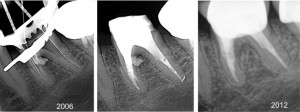

Perforation1